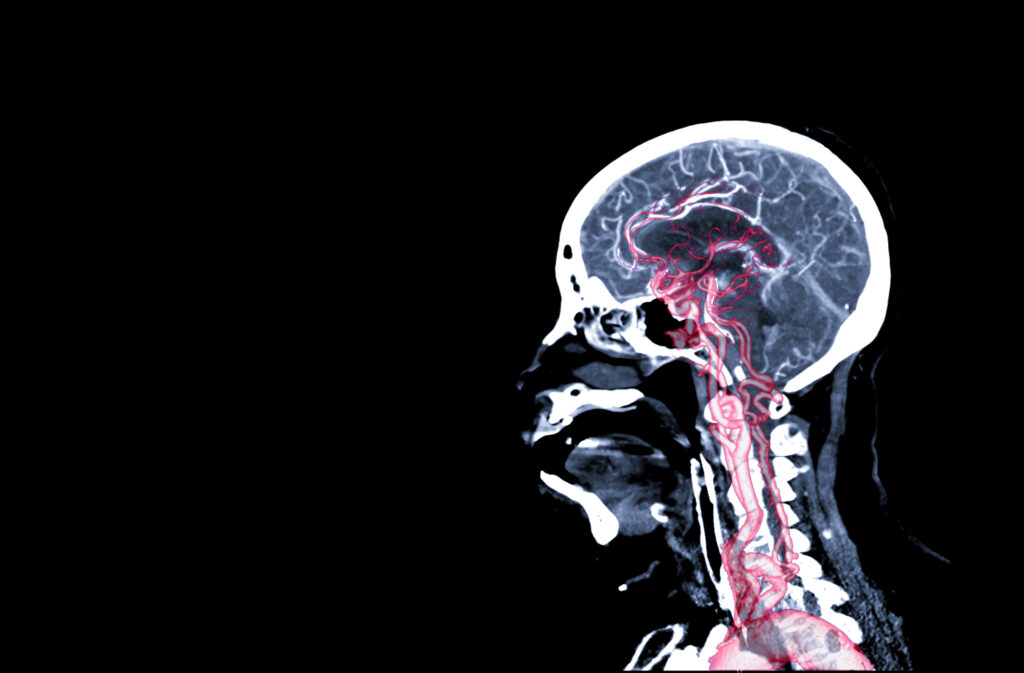

A traumatic brain injury (TBI) is a 치명적인 상해 and is one of the most common injuries suffered in an auto accident. After sustaining a severe brain injury, the journey to full recovery can take a few months, a few years, or a lifetime. No two injuries are the same, and the length of the recovery process will vary from individual to individual.